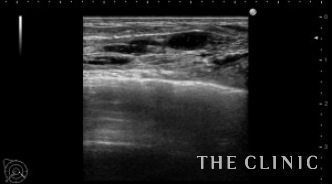

エコー下にヒアルロニダーゼで溶解、吸引しました。

ほとんどなくなりました。